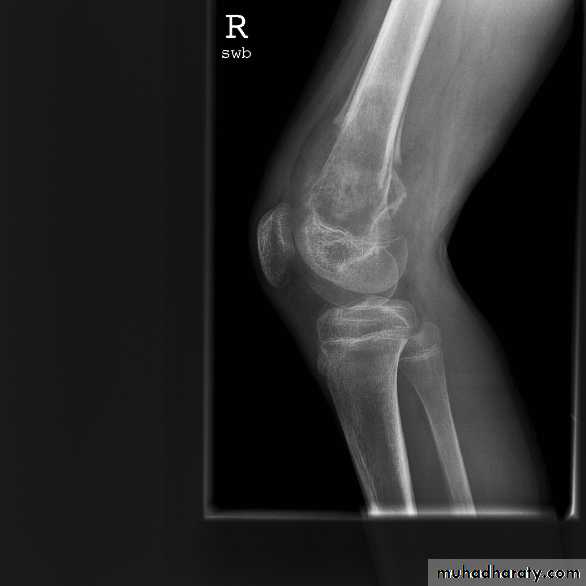

Osteogenic Sarcoma

Metaphyses of long bones:

Distal femur

Proximal tibia

Proximal humerus

Pelvis

Classic X-ray of O.S.:

“Sunburst pattern”Periosteal reaction

Soft tissue mass + calcium

“Sunburst pattern”

Periosteal reaction